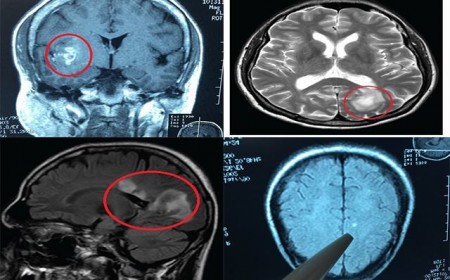

Dấu Hiệu Nhận Biết Sán Lên Não

Dấu hiệu nhận biết sán lên não. Bệnh giun đũa chó mèo hay bà con thường gọi là bệnh sán chó có tên khoa học là Toxocara do một loài giun tròn thường ký sinh ở...

SÁN TRONG NÃO GÂY RA CÁC TRIỆU CHỨNG NHƯ TÂM THẦN